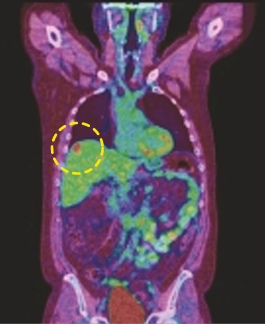

CASE [PET-CT Fusion]

15 min (50%) Scan Without Denoising

15 min (50%) Scan With Denoising

30 min (100%) Scan Standard